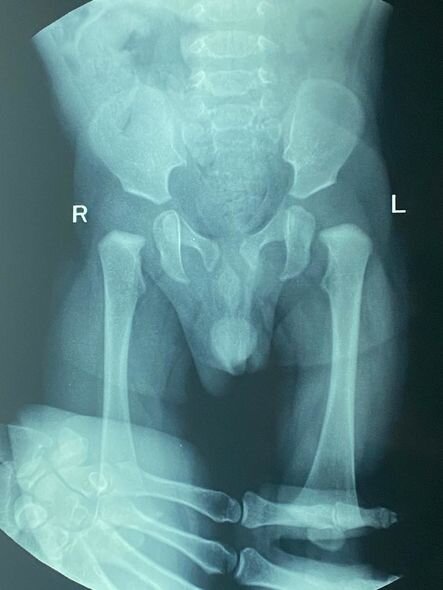

O bildirib ki, övladında anadangəlmə oynaq başcıqları formalaşmayıb.

"Zeyd 8 aylıqdır. Anadan olanda onda oynaq başcıqlarının formalaşmadığını öyrəndik. İlk gündən də müalicələrə başlamışıq. Hazırda Zeyd xüsusi korset taxır. Müalicələrini bir müddət də davam etdirib, daha sonra əməliyyat olunacaq. Hazırda müalicələr üçün 800 manata ehtiyacımız var".